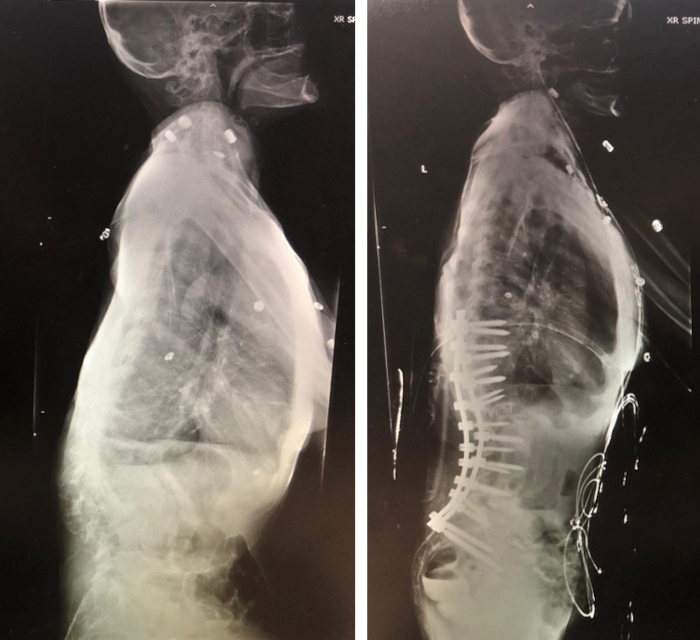

This is a 70-year-old female who has been suffering from progressively worsening back pain for the past decade. She developed a kyphoscoliosis deformity as a result of osteoarthritis and osteopenia consequently causing wedge compressions and lateral spondylolisthesis. She had a very complex spinal deformity in addition to tobacco use, poor bone quality and being malnourished. She also developed painful hip and knee arthritis as a result of compensatory mechanisms to maintain herself upright. She was no longer able to stand without external support and her ambulation was limited to a few feet. She underwent an extensive amount of therapy, bracing, pharmacologic regimen, and multiple pain interventions without any improvement. She has been turned down by prior neurosurgeons and orthopedic spine surgeons, who told her that she was not a surgical candidate given her complexity.

Fortunately, she later met with Dr. Xavier Gaudin who has expertise in the field of scoliosis and spinal deformity. Dr. Gaudin was determined to bring her life back and had a comprehensive treatment plan for her condition. Prior to considering any surgery, she required thorough medical optimization. She began taking Forteo (Teriparatide), a parathyroid hormone to promote bone growth to help her anticipated spinal reconstruction and healing. Additionally, she was started on a nutrition and iron supplementation, and Chantix (Veranicline) for smoking cessation. Following four months of effective optimization, she underwent a T10 to iliac posterior instrumented fusion with L1-2, L2-3 and L3-4 posterior column osteotomies and reduction of her kyphoscoliosis. After uneventful recovery and therapy, she is now able to ambulate fully unassisted and has an increase 7 inches in body height from her spinal reconstruction. She reports her back pain being much improved without requiring any pain medicine, and complete relief of her hip and knee pain. Her postoperative x-rays demonstrated a newly balanced spinopelvic alignment and reduction of her scoliosis curve by greater than 50%. She is to this day fully independent and able to enjoy walks in the park with her grandchildren. The surgery was life changing and brought tears to her eyes.